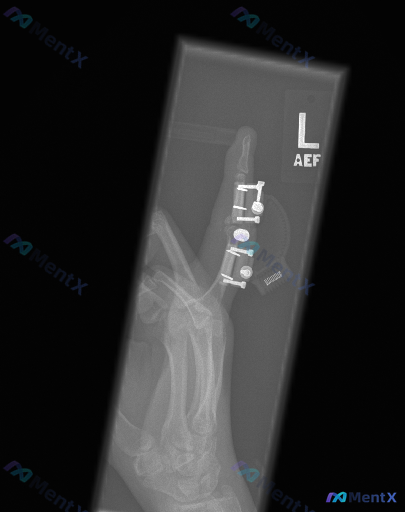

网上看到一份左手拇指的影像资料,描述整理如下,大家一起讨论下: - 这是一张左拇指的侧位/斜位X光片,影像显示清晰 - 可见拇指近节指骨及掌指关节附近有内固定装置(钢板+多枚螺钉,关节附近还有一枚中空/加压装置) - 近节指骨有陈旧性骨折线迹象,骨折断端对位对线尚可 - 无明显螺钉松动、断裂或钢板移...